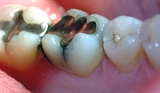

![]()

Bildet viser at den gjenstående amalgamfyllingen er fjernet, og at tannen er bygget opp igjen med en plastfylling.